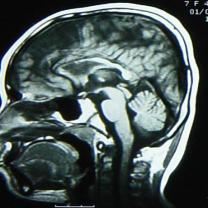

核磁检查:右侧大脑半球皮层大部分呈长T1、长T2信号,其中右额部为与脑脊液信号相同的囊性病变,与右侧脑室相沟通,右侧脑室扩大,左侧脑室大小正常,中线结构居中。MRI诊断:右侧额颞顶枕叶脑软化,右侧脑室穿通畸形(图2)。

图2 MRI显示右侧大脑半球大部分呈长T1、长T2信号,右额部为与脑脊液信号相同的囊性病变,与右侧脑室相沟通,右侧脑室扩大,左侧脑室大小正常,中线结构居中。